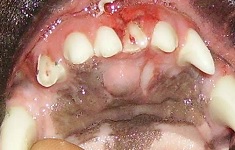

2 A 3 year-old Bulterrier that was involved in a fight.  You inspect the mouth and see 2 fractured teeth (201. 103).

Pulp Exposure Aug 2009-02